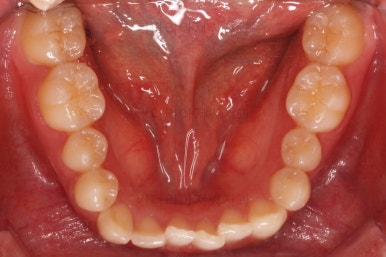

초진 시 입안의 모습이에요.

위아랫니가 모두 삐뚤어요.

특히 앞니가 삐뚤고 위아래 앞니가 고르게 덮여있는게 아니라 뒤죽박죽 엉켜있어서 치아의 마모도 굉장히 많이 되어있는 상태였어요.

이번 환자분은 치아가 삐뚤어 있는 양 + 돌출감을 고려했을 때 비발치로 가능할 것이라고 판단이 되었어요.